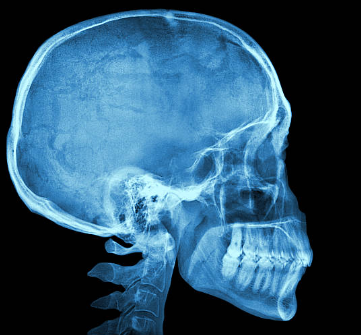

2. 두개골(머리뼈) 방사선 촬영

3. 치아 방사선 촬영